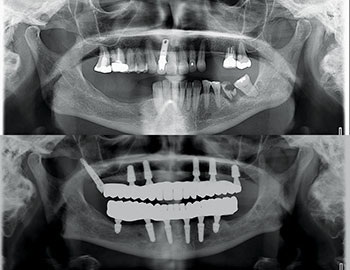

Our patient, a healthy woman in her early 60s, presented with a terminal dentition (Fig. 1) in both arches, collapsed bite, unstable occlusion, midline shift, asymmetric horizontal plane and bone loss (Fig. 2). She was looking for a fixed solution that would give her the confidence to smile, eat and socialize without restrictions. Several previous treatment plans suggested placing provisional dentures as an interim until the implant stabilized, which did not resonate with her desires during the healing phase.

Fig. 1

Fig. 2

Surgery was uneventful. Extractions, site preparations and implant placements went according to plan (Fig. 3). In the maxilla, we placed six implants following the “All-on-6” concept, ensuring posterior spread for optimal load distribution. Six implants were also placed in the mandible following a similar approach.

All implants achieved excellent primary stability (>35 Ncm Torque and ISQ values averaging 72 to75), which allowed us to proceed with immediate loading (Fig. 4). Using SprintRay 3D printed provisionals in OnX Tough 2 resin, we delivered fixed temporaries the next day post-surgery (Figs. 5–8).